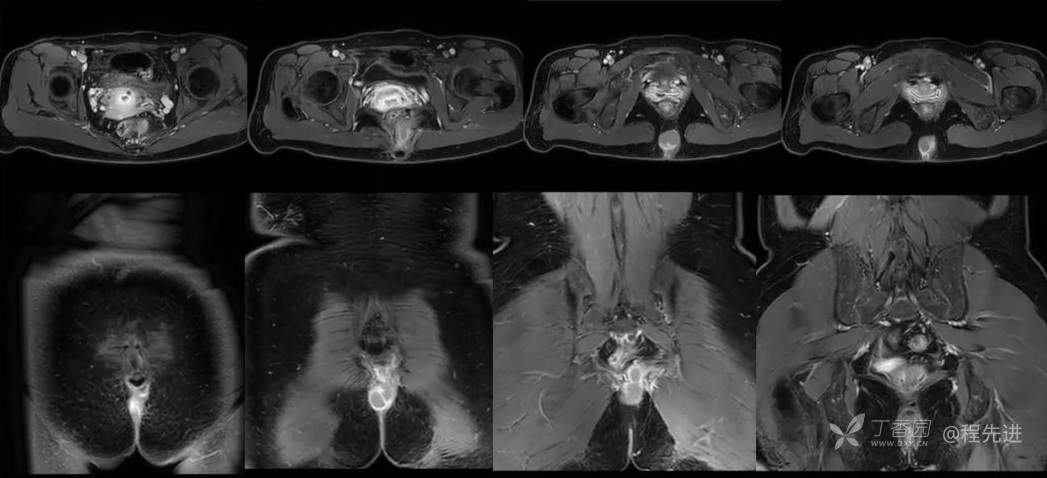

简要病史:3个月前无明显诱因出现骶尾部疼痛,胀痛为主,程度轻微,B超发现肿块3天。

体格检查:脊柱生理曲度存在,无侧弯,无压痛,活动可。尾骨尖右侧旁开2-3CM压痛。